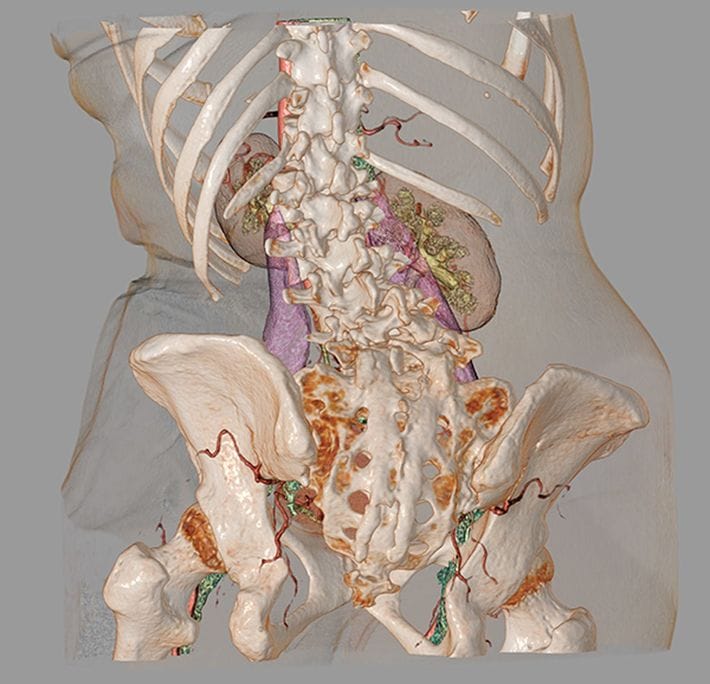

CTとMRIを融合した3D画像は、骨だけでなく椎間板や神経なども確認できるため手術をする際に作成される。(『

カニジル 18杯目

』より)